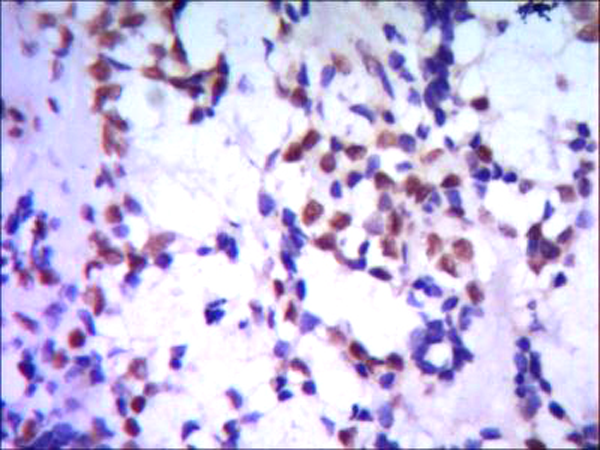

IHC positive control:

Human breast cancer

IHC Recommend dilution:

500-1000